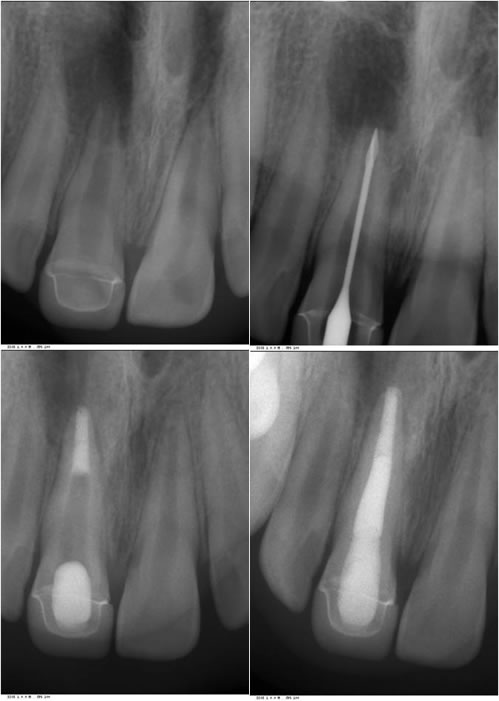

Figures 10,11,12,13: In these figures you can see the pre-op radiograph, the length confirmation used in this case is a gates gliddel because the apex is so large, the MTA fit in the apical 5mm, and the completed case with gutta percha over the MTA and a composite seal of the access point.

1. Once the canal system is properly disinfected and dried an accurate length confirmation or reconfirmation if that has already previous been determined. We will typically use a large piece of gutta percha fit to the proper length and take a radiograph.

5. Take a radiograph of the first pack of MTA to make sure the material is at the correct location apically.

6. If deeper compaction is required based on the radiograph then precede packing deeper and take another x-ray. If the location is correct then incrementally pack more MTA towards the apex until about 4-5mm of MTA is placed.

7. Fill the rest of the canal with material of choice such as a post/core or gutta percha directly onto the MTA.